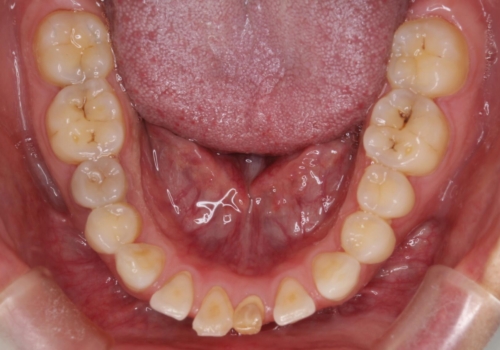

- 歯と歯の間に隙間があることを主訴に来院されました。

短期間での治療終了を希望され、ワイヤー矯正にて治療を行い1年ほどで治療を終了しております。

下顎前歯は矯正後補綴治療を行なっております。